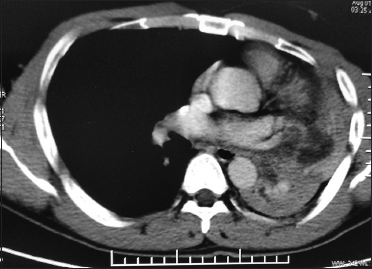

An otherwise well, 34-year-old male with no history of tobacco addiction presented with hemoptysis, intermittent fever, and significant weight loss for 1 year. Examination revealed a 5 cm × 4 cm right axillary lymph node and decreased breath sounds over the left upper lung region, apart from which no other abnormality was detected. Contrast-enhanced computed tomography (CT) of the thorax showed a large neoplasm adjacent to bifurcation of the left main bronchus causing complete collapse of the left lung [Figure 1]. CT-guided biopsy from the lung mass was done for histopathological examination (HPE), which showed features of high-grade myxoid liposarcoma [Figure 2]a] and [Figure 2]b]. Tumor cells were positive for S100 and Ki 67 was 15%. 18 F-fluorodeoxyglucose (FDG) positron emission tomography (PET)-CT scan revealed a mild hypermetabolic predominantly hypodense cystic lesion seen involving the left lung upper lobe inferiorly extending up to the left hilar region, causing abrupt cut-off of main bronchus and encasing upper and lower lobe bronchi causing distal complete collapse consolidation of the left lung upper and lower lobes [Figure 3]a]. Mildly FDG-avid metastatic sites included bilateral axillary lymph nodes, right latissimus dorsi muscle, and hypodense cystic lesion involving pancreas [Figure 3]b] and [Figure 3]c]. In lieu of widely metastatic disease, he was started on palliative chemotherapy with MAID regimen consisting of MESNA, adriamycin, ifosfamide, and dacarbazine chemotherapeutic agents.

| Figure. 1 Contrast-enhanced computed tomography of the thorax showed a large neoplasm adjacent to bifurcation of the left main bronchus causing complete collapse of the left lung